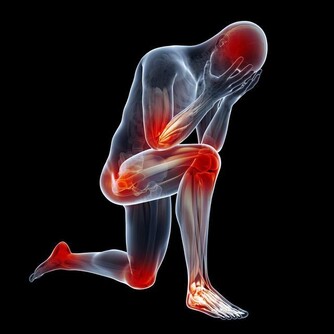

1.修復胰島功能,降低血糖水平。大蒜富含的大蒜素能夠修復胰島細胞,促進其分泌,並增加胰島素的敏感性,從而降低血糖水平。大蒜還能殺死體內的多種病菌,預防感染、並發症。